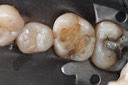

Photos of Clinical Operations

Drs. Peter Kearney, Terry McKay, John St. Germain, and Laurie Vanzella - Mentors